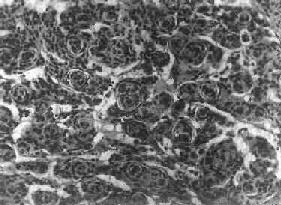

肉眼观,肿为数厘米的结节至巨大块状。分化较好的肿,境界不清;而分化程度较低的肿则境界分明。体灰白色。质地视肿内胶质纤维多少而异,或硬、或软、或呈胶冻状外观,并可形成大小不等的囊腔。由于肿的生长、占位和邻近脑细胞的肿胀,脑的原有结构因受挤压而扭曲变形(图16-23)。

图16-23 星形胶质细胞

左大脑半球肿胀,肿边界不清,部分呈胶冻状